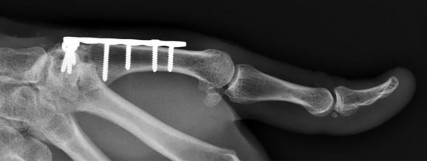

Question 7:

A 25-year-old manual laborer presents with 6 months of radial-sided wrist pain. He recalls a fall on an outstretched hand approximately one year ago but did not seek medical attention at the time. Radiographs demonstrate a scaphoid waist nonunion with sclerosis and cystic changes, but there is no evidence of radioscaphoid or midcarpal arthritis. What is the most appropriate surgical treatment?

Options:

- Four-corner fusion

- Proximal row carpectomy

- Scaphoid excision and four-corner fusion

- Open reduction internal fixation with bone grafting

- Total wrist arthrodesis

Correct Answer: Open reduction internal fixation with bone grafting

Explanation:

The patient has a scaphoid nonunion but lacks degenerative arthritic changes (this is pre-SNAC or SNAC stage 0). In the absence of arthritis, the goal is to obtain union of the scaphoid to prevent the progression of carpal collapse and arthritis. This is best achieved via ORIF with bone grafting (non-vascularized or vascularized, depending on proximal pole viability). Salvage procedures like four-corner fusion or PRC are reserved for established SNAC arthritis.